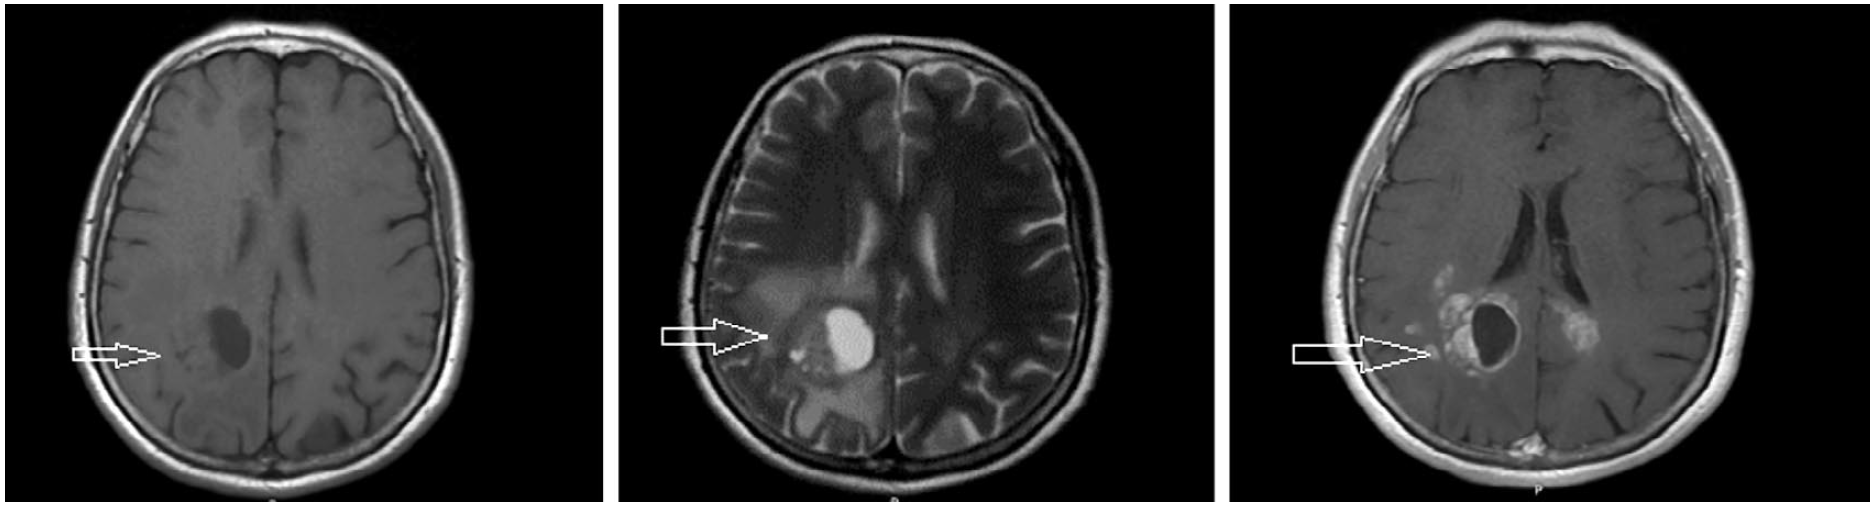

Больная С., 60 лет, считает себя больной на протяжении 3 мес, когда заметила опухолевидное образование в области малой половой губы с изъязвлением. В менопаузе 16 лет. Обратилась за медицинской помощью в онкодиспансер. При цитологическом исследовании отпечатка с опухоли – плоскоклеточный ороговевающий рак. По данным спиральной компьютерной томографии (КТ) органов грудной полости и магнитно-резонансной томографии (МРТ) брюшной полости и малого таза признаков очаговой патологии не выявлено. В январе 2018 г. выполнено оперативное вмешательство в объеме вульвэктомии. При гистологическом исследовании – в подэпителиальных слоях участки крауроза с ростом плоскоклеточного ороговевающего рака. В январе 2020 г. появились слабость в левой верхней и нижней конечности, шаткость при ходьбе, общая слабость. По поводу этого она обратилась к неврологу по месту жительства. При МРТ ГМ с контрастным усилением от 04.02.2020 – в затылочной доле справа, паравентрикулярно, с выраженным перифокальным отеком, определяется кистозно-солидное образование с неровным контуром размером 29×33×65 мм без клинически значимого «масс-эффекта». Срединные структуры не смещены (рис. 1, 2).

Рис. 2. Больная С., 60 лет. На сагиттальной и корональной постконтрастных магнитно-резонансных томограммах ГМ в затылочной доле паравентрикулярно справа определяется кистозно-солидное образование размером 29×33×65 мм с неровным контуром и выраженным перифокальным отеком, без клинически значимого «масс-эффекта».

Fig. 2. Patient S., 60 years old. On sagittal and coronal postcontrast magnetic resonance imaging of the brain in the occipital lobe, paraventricular, to the right is determined cystic-solid formation size 29×33×65 mm with rough edges and with intensive perifocal edema, without clinically significant mass-effect.